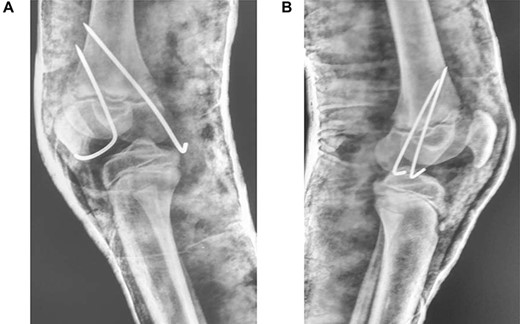

A 9-year-old male presented to the ER within 6 h of injury to both knees, with swelling, restricted movements and tenderness bilaterally. Assessment demonstrated distal pulses in both legs. Initial management was with pain relief—neurological status was not assessed due to pain. A history of direct fall of a concrete block onto both knees whilst sitting with legs extended and raised on a stool at a building site, leading to a forced hyperextension injury, was elicited. The patient received no treatment before presenting to our unit. Radiography suggested bilateral completely displaced Salter-Harris Type I fractures (Fig 1A–C). All routine laboratory and metabolic profiles performed were within normal ranges. Patient was transferred to theatre immediately after radiography for a closed reduction.

(A) Lateral view of right knee at presentation, (B) lateral view of left knee at presentation, (C) frontal view of both knees at presentation